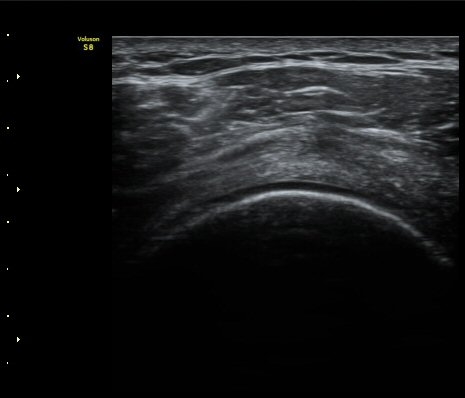

±Ø»ó°Ç Á¾´Ü¸é°Ë»ç½Ã ±Ø»ó°ÇÀÇ Ç¥Ãþ¿¡¼­ °üÂûµÇ´Â °ßºÀ¿À±¸µ¹±â Ⱦ´Ü¸é°Ë»ç»ó¿¡¼­

ÀδëÀÇ ºñÈİ¡ °üÂûµÈ´Ù(»çÁø 4). ±Ø»ê°ÇÀÇ Á¾´Ü¸é°Ë»ç¿Í Ⱦ´Ü¸é°Ë»ç¿¡¼­ ±Ø»ê°Ç ½ÉÃþ¿¡

Àú¿¡ÄÚ º´º¯ÀÌ °üÂûµÈ´Ù(»çÁø 5, 6).